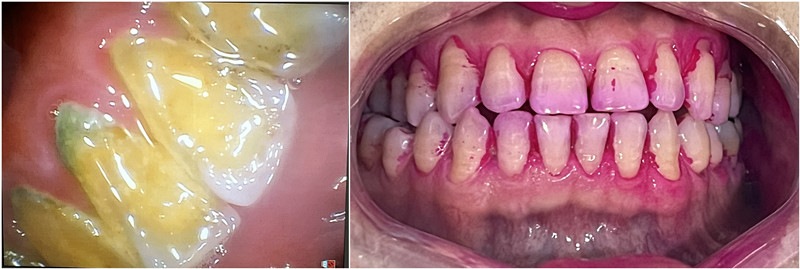

陈女士近日刷牙出血,自觉口臭,影响社交,近日来我科检查发现口内大量结石,需要进行洁治,由于从小就对牙科治疗非常恐惧,最后陈女士选择了舒适化洁牙。陈女士表示,舒适化洁牙洗牙过程几乎没有酸痛,且喷砂后牙面光滑,体验感很好。

洁牙前,牙结石多,牙龈红肿,色素沉着

洁牙后,牙面光洁